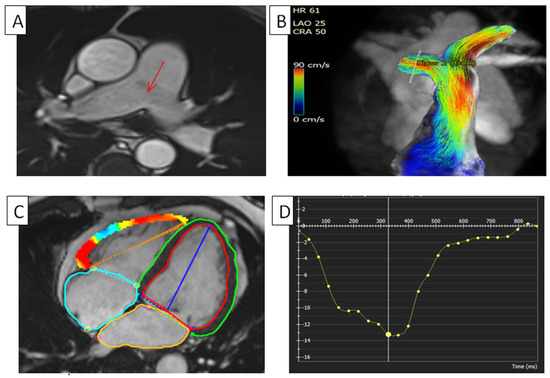

Figure 2.

RV in pulmonary hypertension. (A) Dilated pulmonary artery in can be seen in a patient with pulmonary hypertension using short-axis cine cMRI. The arrow is pointing to the dilated pulmonary artery. (B) Pulmonary artery flow, using cMRI phase contrast, can be seen in a patient with pulmonary hypertension. (C) Four-dimensional myocardial FTI on a short-axis cine SSFP image. (D) RV global longitudinal strain in a patient with pulmonary hypertension. Longitudinal values are usually in the negative range. On the graph, the vertical axis shows the longitudinal strain (14.1%) and the horizontal axis shows the time in milliseconds. FTI, feature tracking imaging; RV, right ventricle; cMRI, cardiac magnetic resonance imaging; SSFP, steady-state free precession.

Recently, three-dimensional (3D) phase-contrast magnetic resonance imaging, known as 4D flow cMRI, has been established as a minimally invasive technique for quantitatively assessing the blood flow through the heart and major arteries during cardiac cycles. Additionally, the distinctive blood flow seen in pulmonary hypertension may be shown using 4D flow cMRI. This technique may serve as a valuable, noninvasive, nonionizing approach for diagnosing and monitoring patients with PAH [30]. Numerous quantitative cMRI parameters have been documented to exhibit significant alterations in pulmonary hypertension, facilitating the precise assessment of cardiac function and morphology. Notably, the emergence of the vortical blood flow in the main pulmonary artery has been evaluated using 4D flow imaging. Furthermore, the length of the vortical blood flow was proposed as a viable 4D flow measure for the precise noninvasive assessment of PAH, making cMRI 4D flow imaging very compelling for noninvasive PAH monitoring [31]. Pulmonary artery hypertension observed using 4D flow can be seen in Figure 2.